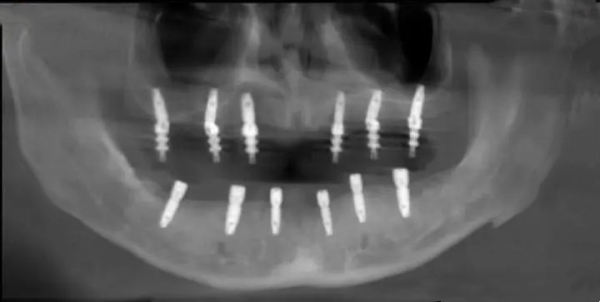

醫(yī)院配備國(guó)內(nèi)外高端的CBCT三維影像系統(tǒng)和數(shù)字化導(dǎo)板技術(shù),可實(shí)現(xiàn)穩(wěn)準(zhǔn)種植,誤差控制在0.1mm以內(nèi)。手術(shù)室達(dá)到潔凈標(biāo)準(zhǔn),確保種植過程可靠無菌。

- 每年拍攝一次X光片檢查骨結(jié)合情況